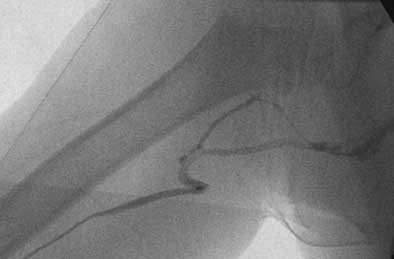

| Fluoroscopic spot image from a PICC placement at Children's Hospital in Cincinnati involving a child who has undergone prior PICC placements. After gaining ultrasound-guided access to the right basilic vein, the catheter would only thread to the upper arm, at which point it would buckle. Contrast injection revealed venous tortuosity. All images courtesy of Dr. John Racadio. |